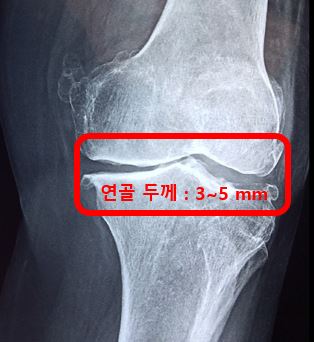

관절 연골은 물 70%, 나머지 30%는 II형 콜라겐, 프로테오글리칸 및 히알루론산으로 구성되어 있습니다. II형 콜라겐은 연골의 구조를 유지하는 역할을 합니다.